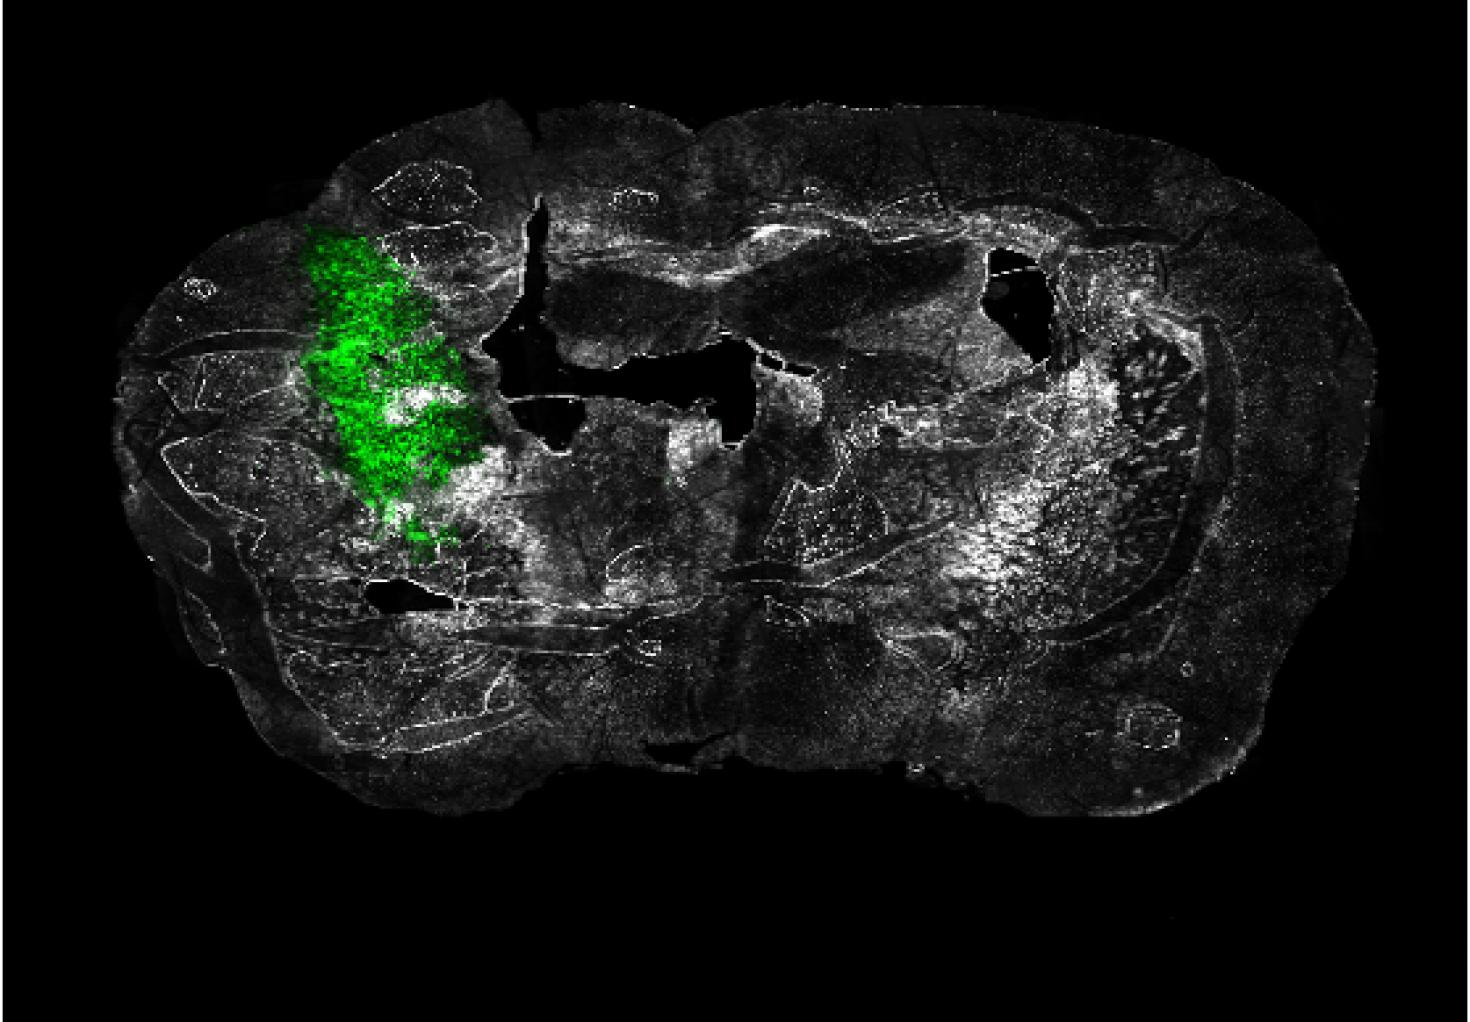

"Ex vivo coronal section of glioma cells, labeled with GFP (green), in a mouse model of glioblastoma (GBM) on day 14 of tumor development."

Image taken on Axioscan.

Author: Urbi Saha - Andrew Smith's Lab